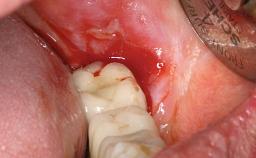

A 77-year-old male patient was referred for the management of frequent and repeated acrylic fracture of his existing mandibular fixed full-arch implant-supported metal/acrylic prosthesis. He also complained about softtissue soreness and the lack of retention and stability of his maxillary removable partial metal/acrylic prosthesis. Both prostheses had been delivered two years previously as part of his full-mouth rehabilitation (caries, tooth wear, tooth fracture). His medical history revealed high blood pressure, controlled with the use of antihypertensive medication.